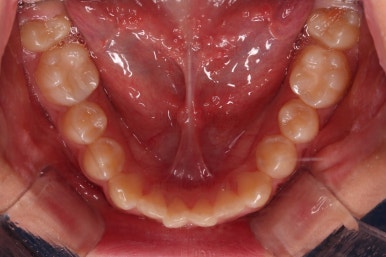

3. 치료경과

악궁확장부터 시행합니다.

확장이 잘 되어 앞니 사이에 틈새도 잘 벌어진 것이 확인되고요.

적절한 시기에 시차를 두고 순차적으로 브라켓을 부착합니다.

이번 환자분이 선택한 브라켓은 자가결찰 메탈의 한 종류인 엠파워 메탈 장치였습니다.

흔히들 아시는 클리피씨와 같은 자가결찰 타입이며, 성분만 금속성이라 눈에 좀 더 잘 띈다는 특징이 있지만 부피도 좀 더 작고 튼튼하며 좀 더 저렴한 장점이 있습니다.

적절한 시기에 아랫니도 장치를 구성하고요.

과개교합 및 앵글씨 2급 부정교합 개선을 도와주는 장치도 보조적으로 활용해 주었습니다.

가지런한 느낌은 좋아졌고, 과개교합도 깔끔하게 개선이 되었습니다.

이제부터는 부정교합을 개선하면서 위아래 어금니 맞물림을 개선해 나갑니다.

성인이었다면 미니스크류 혹은 발치가 필요한 상황이었을 것이나 아직 청소년기이고 약간의 성장여력을 활용할 수 있는 상황이었으므로 미니스크류나 발치 없이 개선해 나가보기로 했습니다.